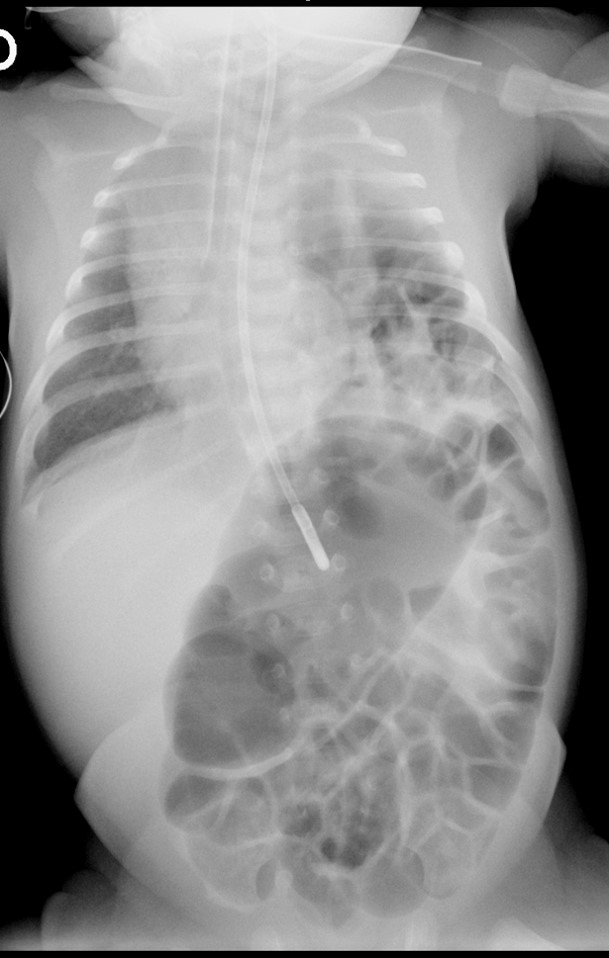

Hernia de Bochdalek en niño de diez días de vida.

La hernia diafragmática más frecuente es la de Bochdalek, por el foramen pleuroperitoneal posterior, habitualmente izquierdo. En la radiografía se presenta como una masa intratorácica con asas intestinales en su interior. La hernia de Morgagni se localiza anterior y derecha, y es menos frecuente.